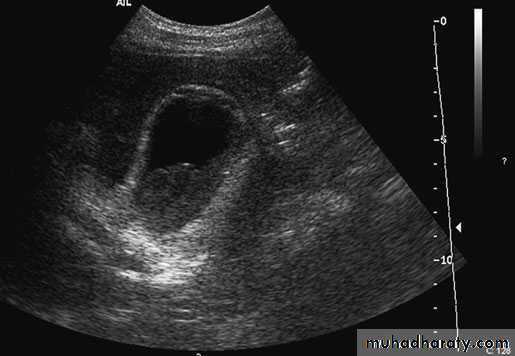

Cholecystitis. Ultrasound demonstrates pericholecysticfluid (thin arrow), gall bladder wall (thick arrow) and biliary sludge